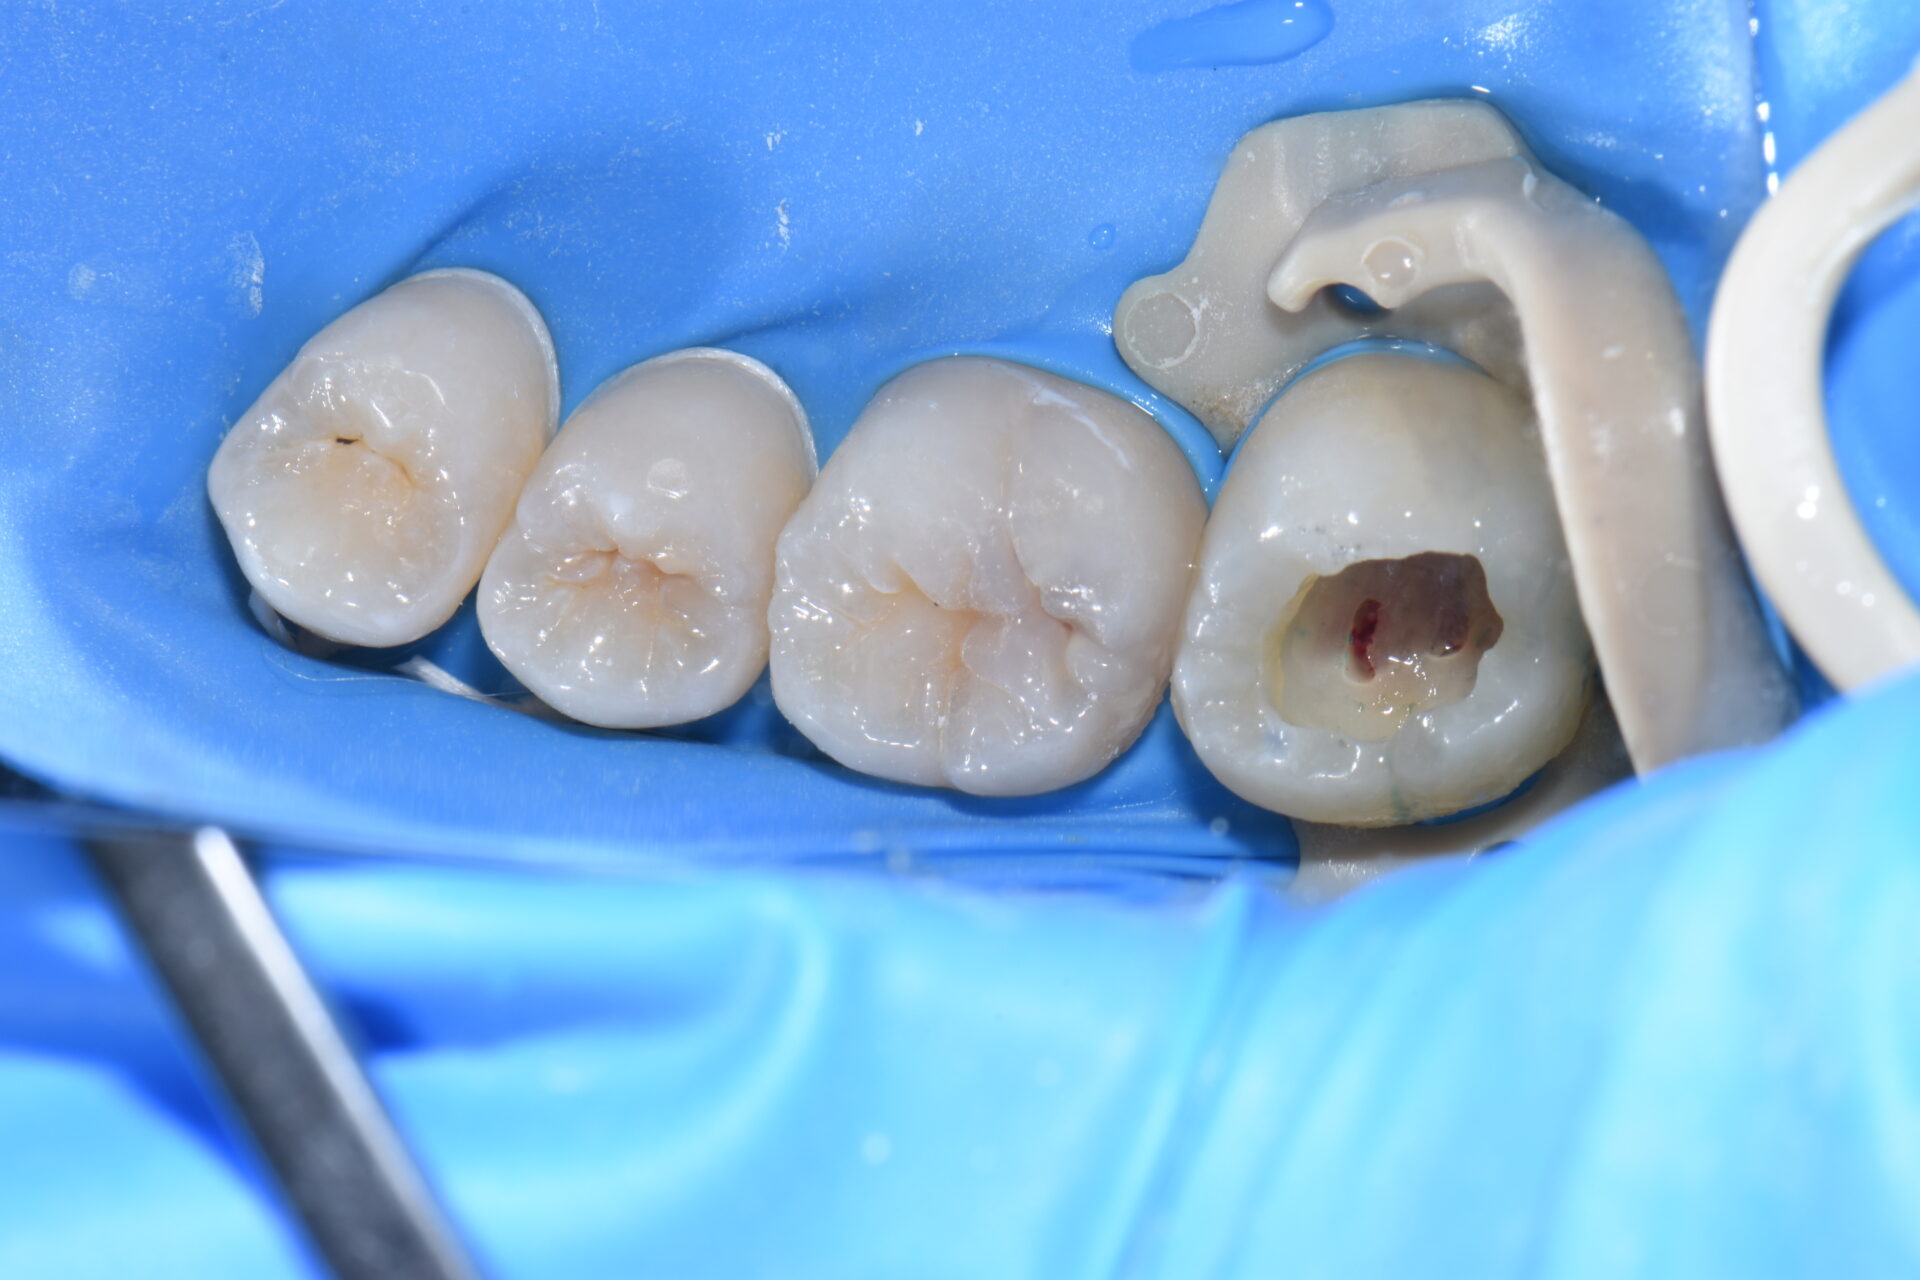

術中 虫歯を除去していくと

術中 神経にまでおよぶ深い虫歯でした。赤く出血しているところが神経です。

当院では虫歯は細菌感染であり綺麗に除去しなけらばならないと考えています。

ラバーダム防湿下で呼気や唾液、口腔内細菌にさらされることなく処置すれば高確率で

神経を温存できます。

神経を取らずにMTAで歯髄を保護しダイレクトボンディング修復していきます。